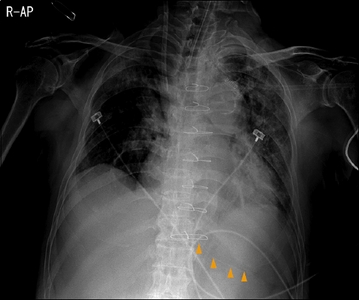

In this patient, the tip of the former Levin tube had been positioned in the stomach, as noted in a retrospective review of chest radiographs. However, the portion of the tube that reached inside the stomach was about 15 cm in length (Fig. 4). Therefore, it is reasonable to assume that some of the side holes of the tube were located above the GEJ.

Fig. 4

The tip of the Levin tube located in the stomach (arrowheads), but the portion of the tube inside the stomach was about 15 cm.

JCN_10_025_fig_4.jpg